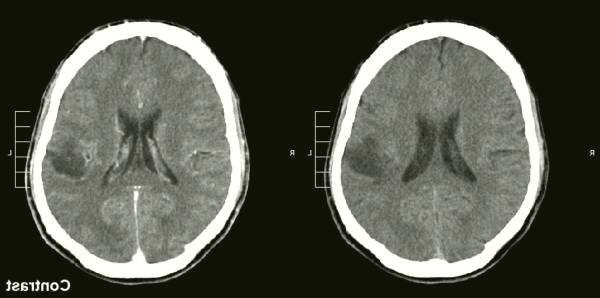

این نوع آزمایشات ( MRI )، معمولا برای تشخیص و بررسی تومور مغزی استفاده می شود. در برخی موارد، ممکن است رنگ از طریق سیاه رگ به بازوی شما در حین ام آر آی تزریق شود. تعدادی از اجزای اسکن ام آر آی - از جمله ام آر آی عملکردی، ام آر آی پرفوژن و ام آر آی طیف سنجی رزونانس مغناطیسی- می توانند به پزشک شما کمک کنند، تا تومور را ارزیابی کرده و درمان را برنامه ریزی کنند.

گاهی اوقات دیگر آزمایش های تصویربرداری از جمله پرتونگاری کامپیوتری ( CT ) توصیه می شود. توموگرافی انتشار پوزیترون (PET) برای تصویربرداری از مغز مورد استفاده قرار می گیرد، اما به طور کلی فقط برای ایجاد تصاویر سرطان مغز مفید تست و برای انواع دیگر سرطان مفید نیست.